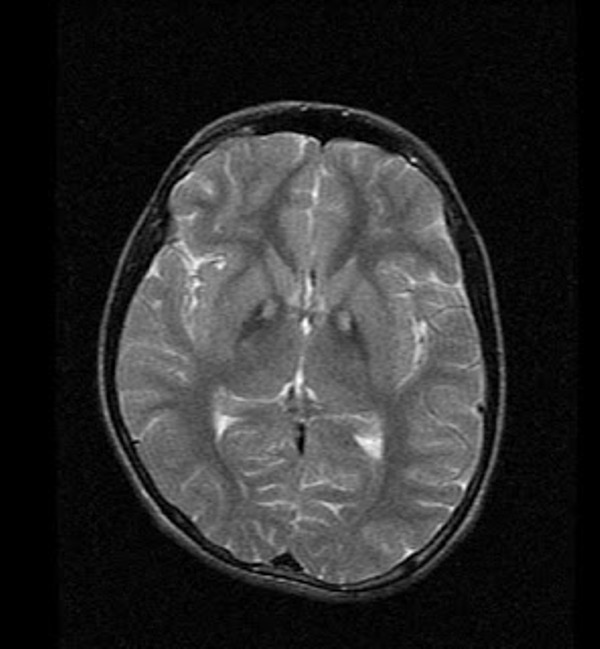

MRI advances diagnosis of Hallervorden-Spatz syndrome,

MRI advances diagnosis of Hallervorden-Spatz syndrome, Hallervorden-Spatz Syndrome - Body MR Case Studies - CTisus,

Hallervorden-Spatz Syndrome - Body MR Case Studies - CTisus, Hallervorden-Spatz Disease – Symptoms and Causes - Dr. Anki,

Hallervorden-Spatz Disease – Symptoms and Causes - Dr. Anki, Renaming of Hallervorden–Spatz disease: the second man,

Renaming of Hallervorden–Spatz disease: the second man, EYE OF THE TIGHER SIGN : Eye of the tiger sign is seen in

EYE OF THE TIGHER SIGN : Eye of the tiger sign is seen in医科プロバイオティクス学/古賀泰裕(著者)